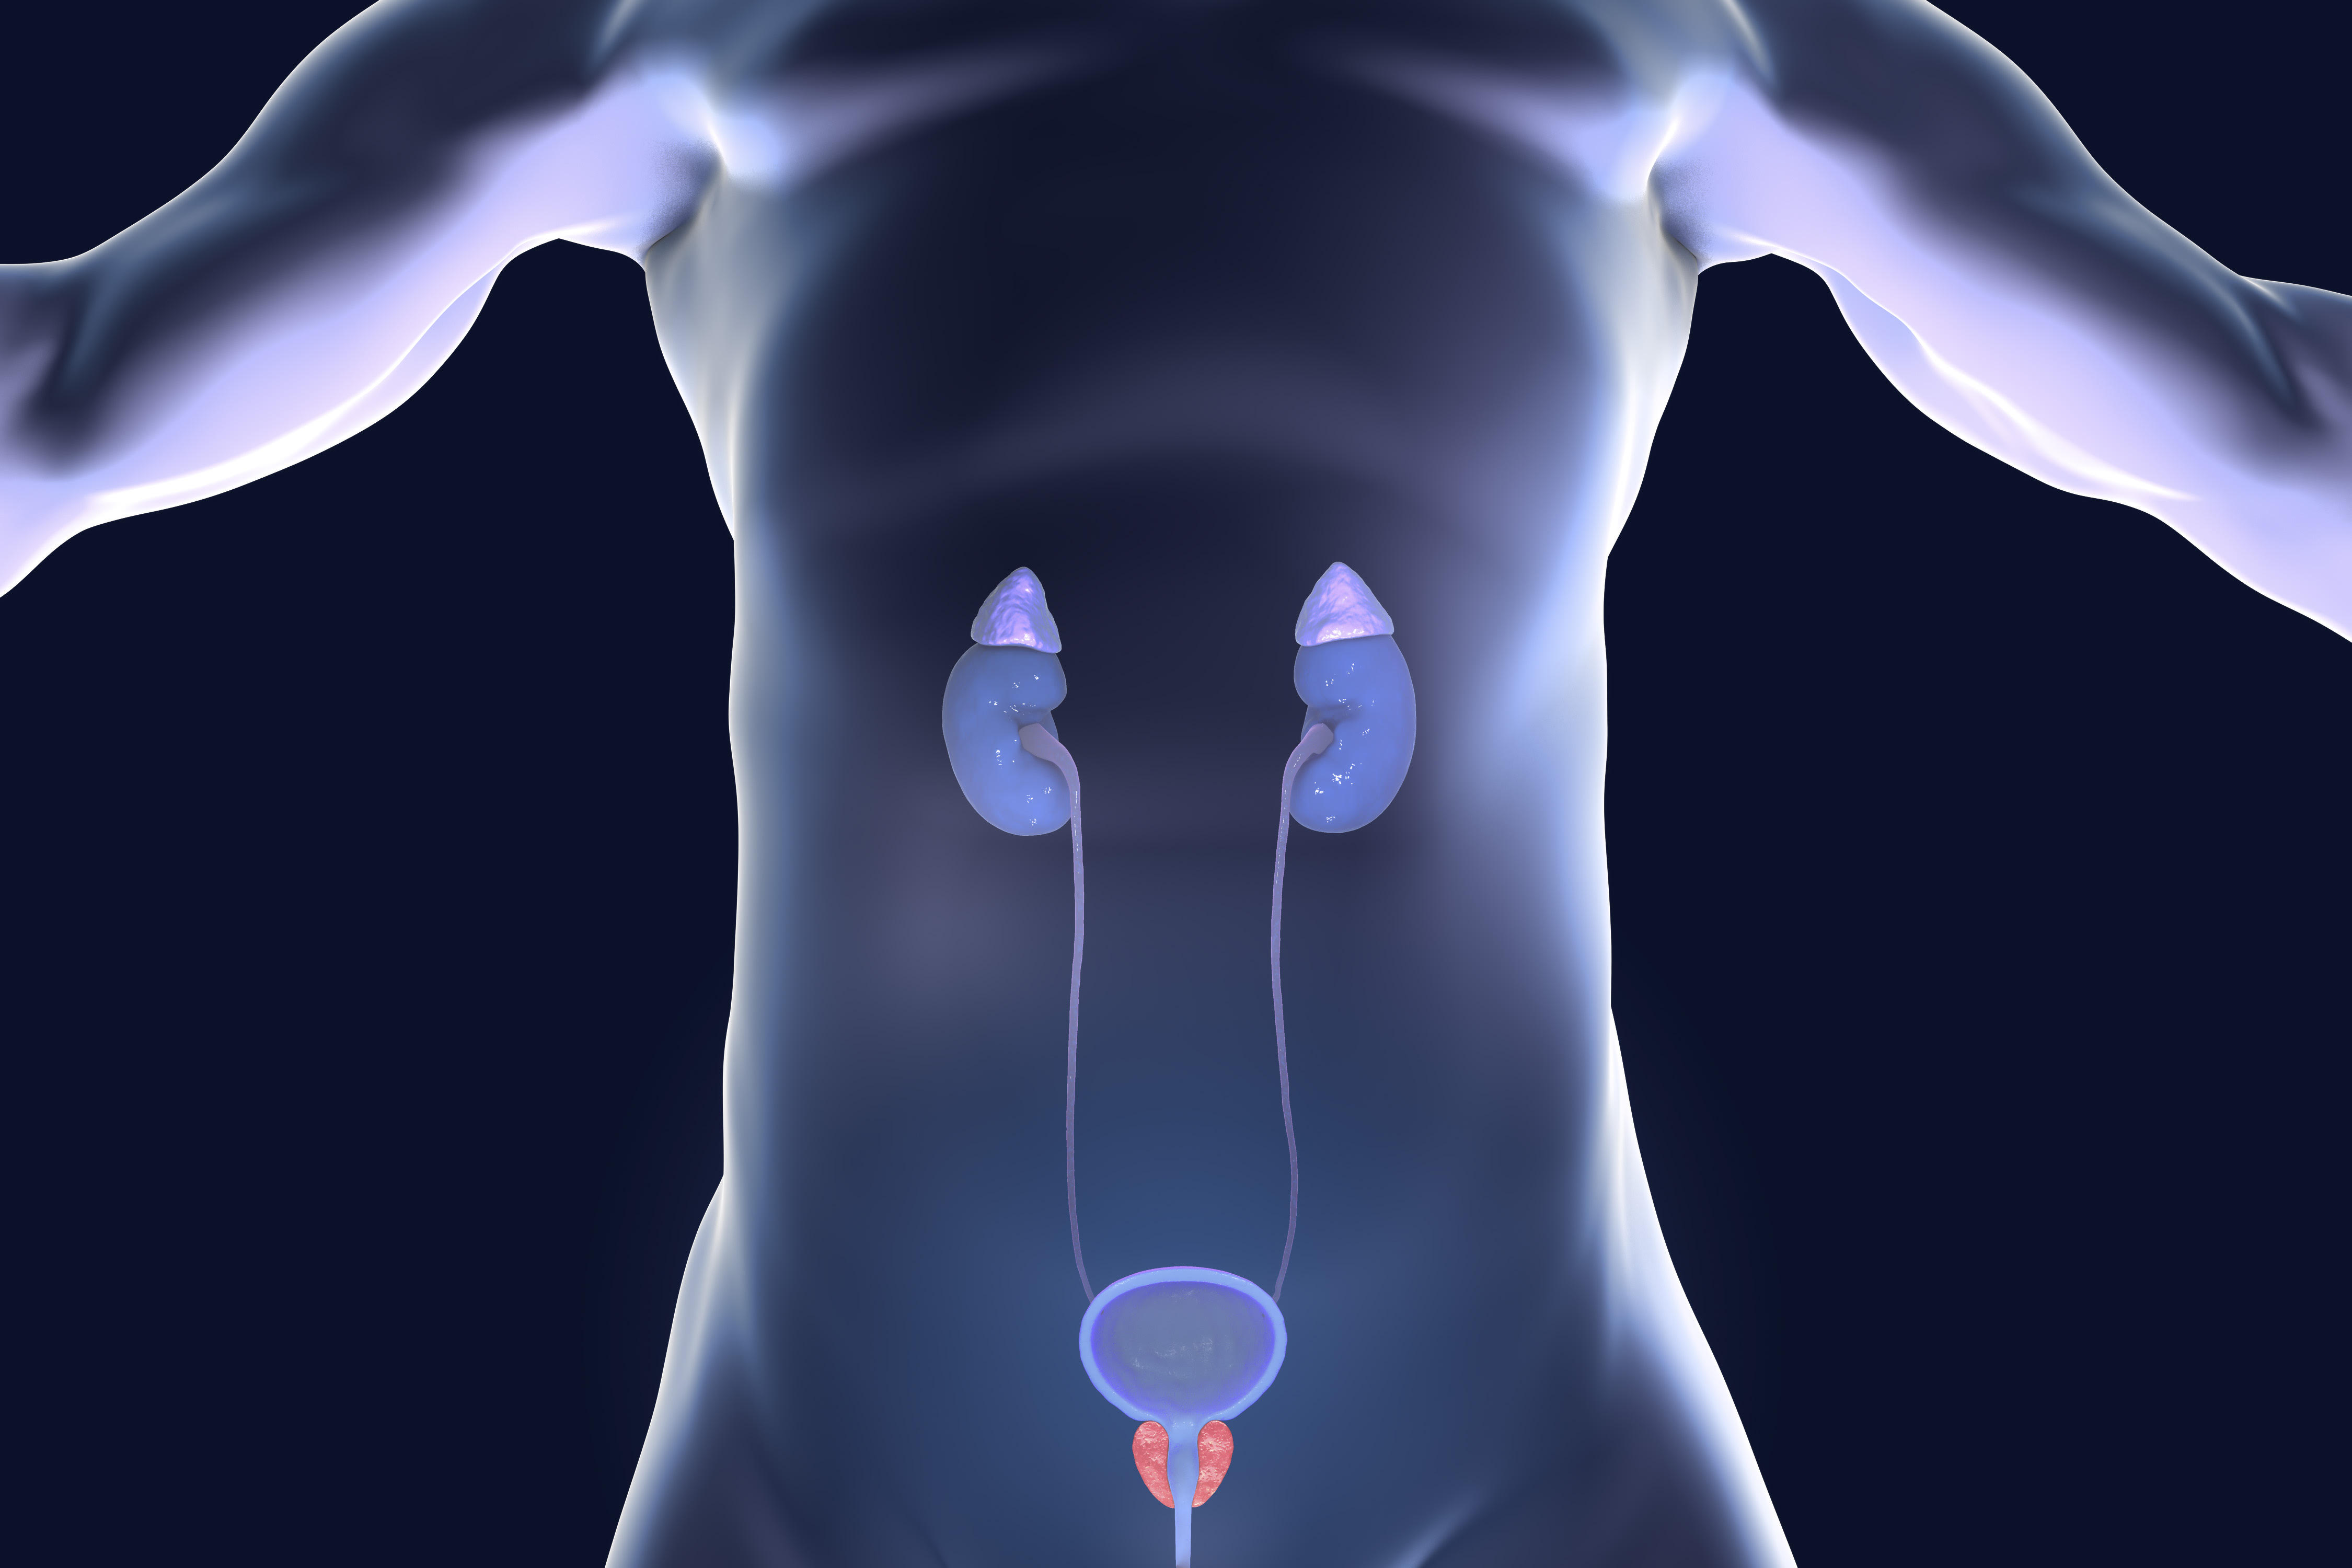

Overview of the Prostate

The prostate is a small gland in the male reproductive system. The main role of the prostate is to produce the fluid that protects and gives nutrients to sperm. The prostate sits underneath the bladder and surrounds the top part of the urethra, which carries urine from the bladder.

Overview of the Prostate and Surrounding Structures

The prostate is approximately the size of a walnut in men younger than 30 years old; as men age, the prostate grows larger. At puberty, testosterone levels in boys start to increase and the prostate grows to about eight times its size. The prostate continues to grow, doubling in size between the ages of 21 and 50 years, and almost doubles again in size between the ages of 50 and 80 years. Prostate size is generally measured in volume using milliliters, or ml.